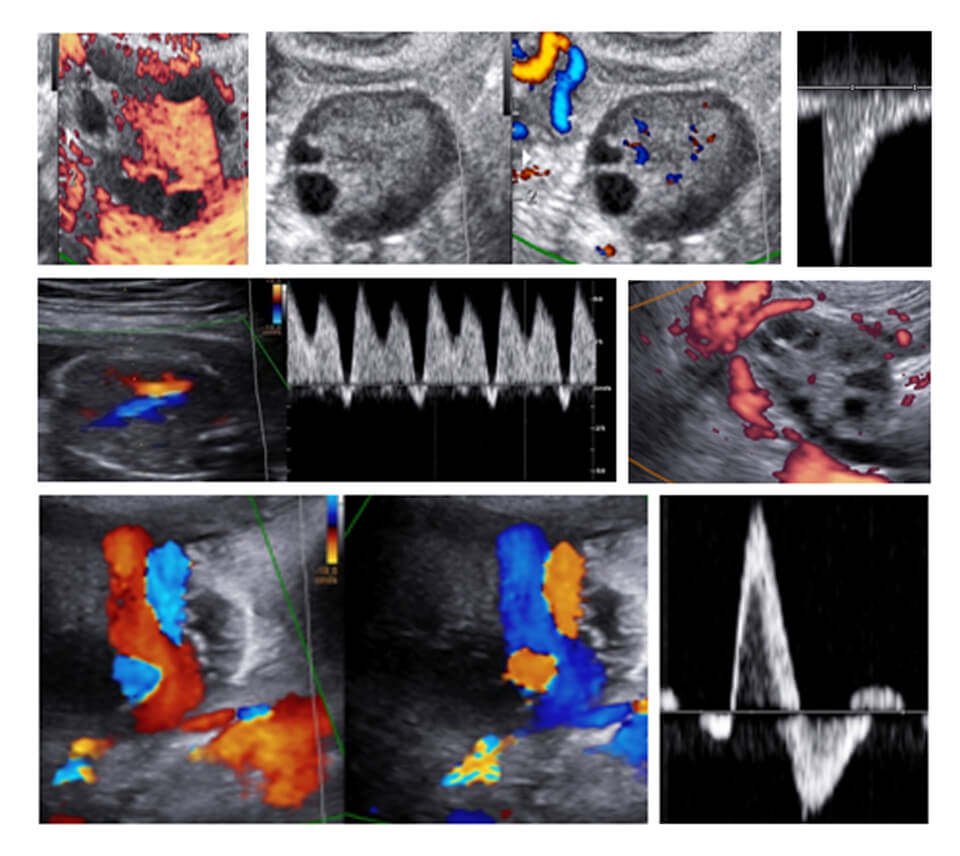

COLOR DOPPLER CLUB

CDC : INFERTILITY

BASELINE SCAN

ENDOMETRIAL FLOW OVARIAN STROMAL FLOW

FOLLICLE MONITORING

ENDOMETRIAL ZONAL VASCULARITY UTERINE ARTERY DOPPLER PERI-FOLLICULAR VASCULARISATION FOLLICLE PSV

LUTEAL PHASE

CORPUS LUTEAL FLOW

CDC : GYNECOLOGY

ENDOMETRIUM

FLOW IN DIFFERENT PHASES POLYP/HYPERPLASIA/

MALIGNANCY/ADHESION

MYOMETRIUM

FIBROIDS ADENOMYOSIS

ADNEXA

CDC : PREGNENCY (04-14)

04-10 WEEKS

CORPUS LUTEUM

RPOC

MISSED

MOLAR